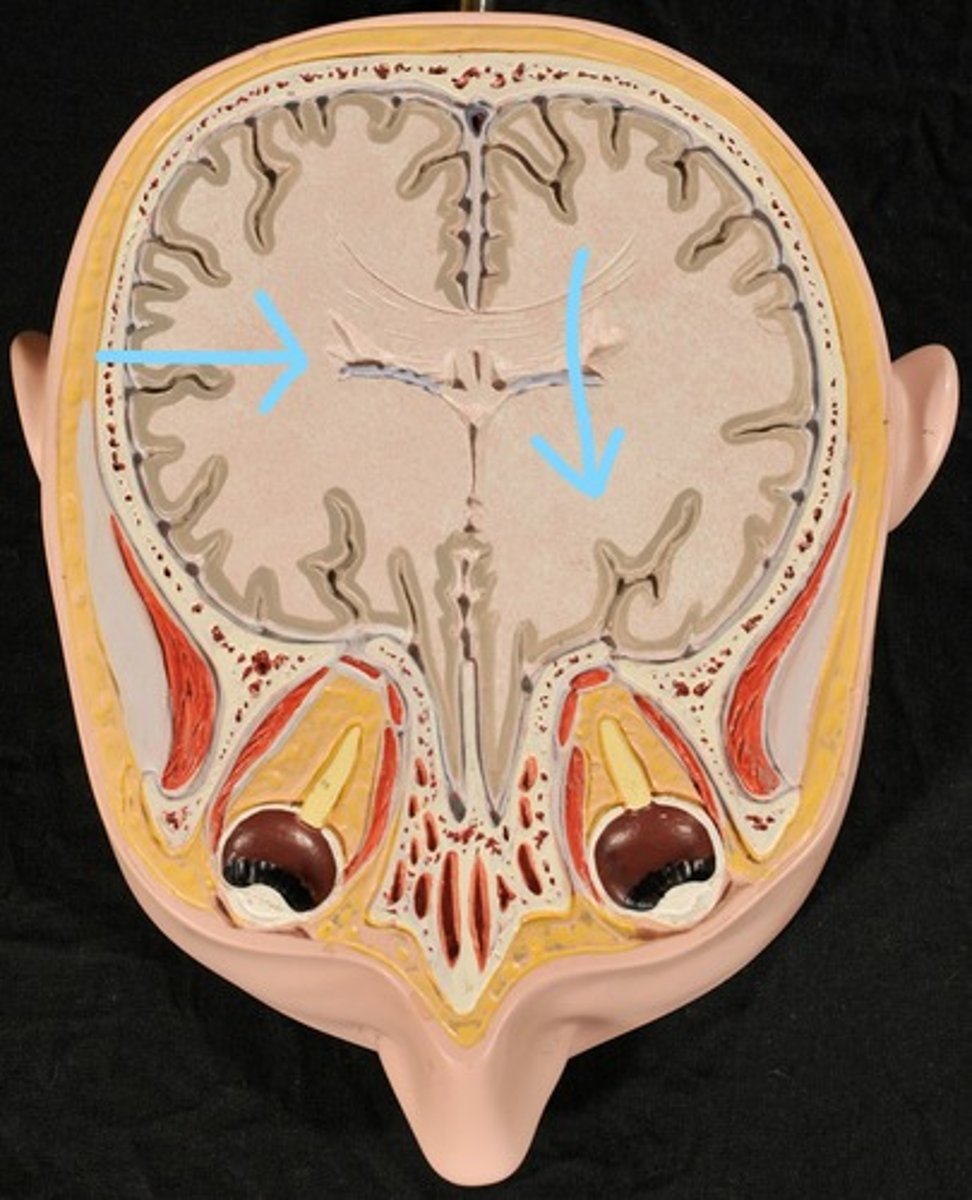

Cerebral Cortex (gray matter) (Slice 2)

Cerebral Medulla (white matter) (Slice 2)

Right & Left Parietal Lobes (Slice 2)

Third Ventricle (Slice 2)

Right & Left Lateral Ventricles (Slice 2)

Choroid Plexus (blue) (Slice 2)